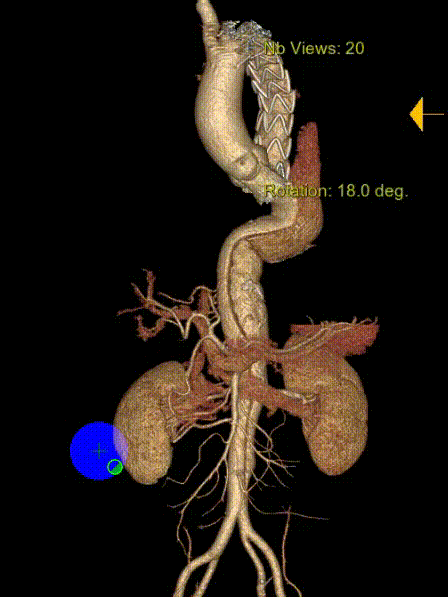

术后8年随访发现假腔明显扩大,最大直径达96mm,伴胸背疼痛,有手术干预指征。

再干预方案:弹簧圈栓塞分支血管(LSA栓塞),覆膜支架+封堵器+弹簧圈覆盖左肾动脉破口。

修复结果:进入假腔血流明显减少,胸背疼痛症状明显缓解。

二次手术前CTA